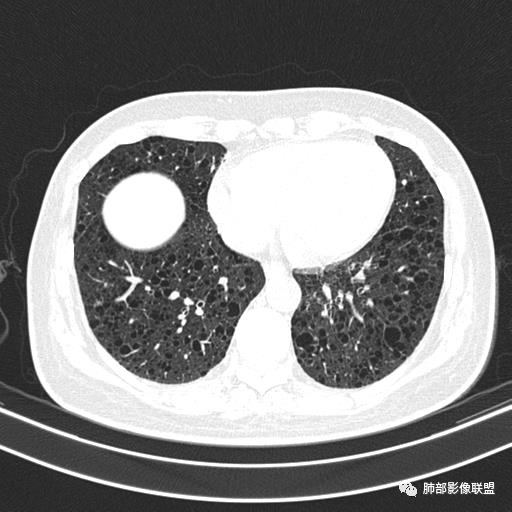

双肺多发大小相近的囊状影,分布趋势趋于一致,中年女性,考虑LAM。部分囊内见血管及分隔影,小叶中心性肺气肿代排

CT表现:双肺弥漫大小不等的薄壁囊腔,囊壁<2mm,外形规则,血管影多位于囊腔周围,囊腔之间肺组织正常,随着疾病进展到晚期,囊腔变大、增多,不可胜数,囊腔可融合成较大的囊,与肺气肿相似,形成间质性肺纤维化。部分病例可出现结节影。

1.小叶中心性肺气肿:上肺为主,无壁,中央见小血管影,位于小叶核心周围,部分血管可推移到边缘,周围肺组织正常